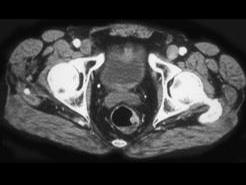

问题 男性,41岁,血便,肛诊触及左侧直肠壁一质硬小结节,结合CT所见应考虑为 ( )

选项 A、直肠转移瘤 B、直肠间质瘤 C、直肠癌 D、直肠息肉 E、直肠腺瘤

答案 C